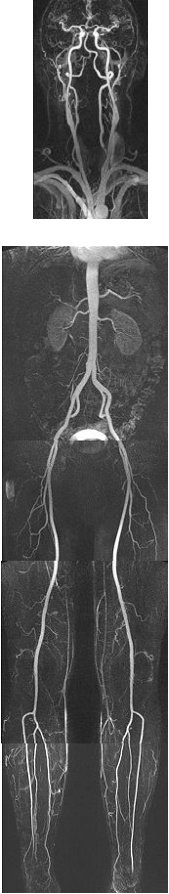

In einem Untersuchungsgang können die Arterien des ganzen Körpers detailgenau dargestellt werden. Die Arteriosklerose, nach wie vor die gefährlichste Zivilisationskrankheit, betrifft meist gleichzeitig mehrere Gefäßterritorien mit schwerwiegenden Folgen: die Herzkranzgefäße (Herzinfarkt), die das Gehirn versorgenden Gefäße des Halses (Schlaganfall), die Nierenarterien (Nierenversagen, Bluthochdruck), die Bauchschlagader (Aortenaneurysma) und die Arterien des Beckens und der Beine (Durchblutungsstörungen bis zur Amputation). Durch die Erkennung von Einengungen dieser Gefäße kann frühzeitig eine zielgerichtete Behandlung eingeleitet werden, ehe es zu den genannten, teilweise katastrophalen Folgen kommt (Abbildung 1).